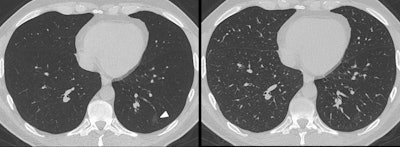

A 37-year-old man presented to the emergency department with cough and fever. An immediate CT scan was performed due to suspected pulmonary COVID-19 manifestation. Left: The axial minimum intensity projection (MinIP) reconstruction shows focal subtle ground-glass opacity in the left lower lung lobe (arrowhead) suspicious for early-stage pulmonary COVID-19, which was missed on axial multiplanar reformat series (Right) by 6/6 readers in this study. Real-time reverse transcription polymerase chain reaction confirmed severe acute respiratory syndrome coronavirus 2 infection. All figures courtesy of EJR and Dr. Christian Booz and colleagues.Some studies suggest that chest CT is more sensitive when it comes to diagnosing COVID-19 than reverse transcription polymerase chain reaction (RT-PCR) testing; this sensitivity is due to the modality's ability to identify ground-glass opacity, a key indicator of the disease. But standard transverse CT reconstructions and MPRs can miss ground-glass opacities due to overlay by vascular structures -- and that's bad news for patients, the team wrote.